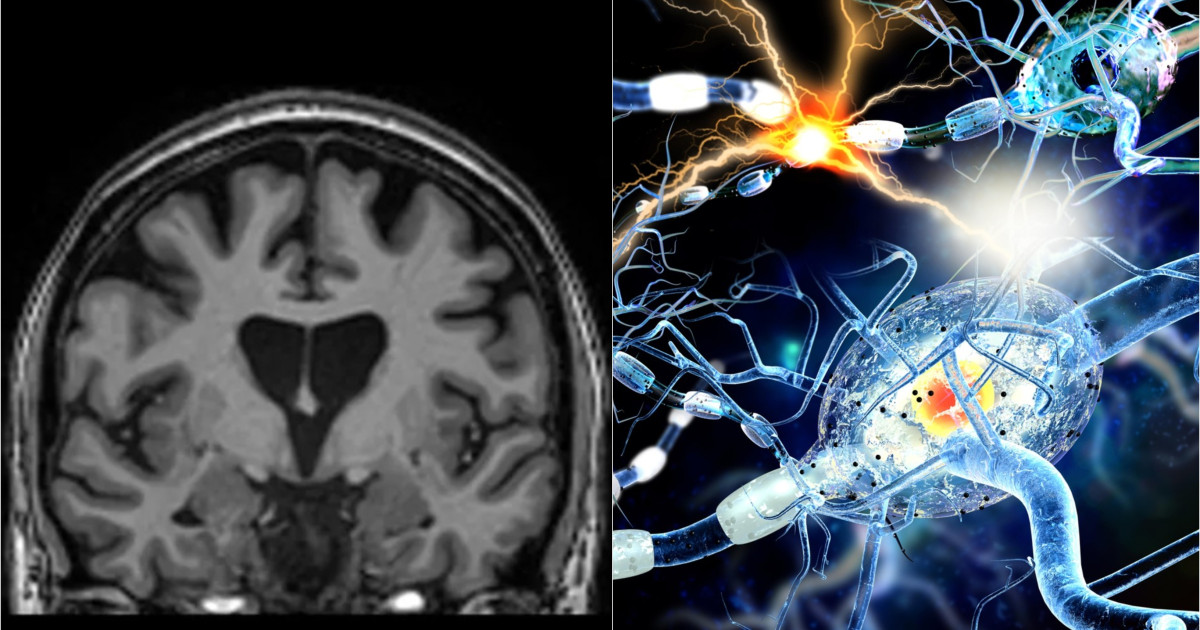

Studiu: Covid-19 poate lăsa modificări detectabile în creier, chiar şi după recuperare completă

Cercetarea realizată la Universitatea Griffith a folosit imagistică prin rezonanță magnetică pentru a identifica modificări cerebrale la persoane care au avut Covid-19, chiar și când acestea nu mai prezentau simptome.

Schimbările la nivelul țesutului cerebral au fost asociate cu severitatea simptomelor în sindromul post-Covid, indicând efecte persistente asupra sănătății creierului.

Rezultatele susțin ipoteze privind influențe pe termen lung ale infecției cu SARS-CoV-2 asupra funcțiilor cognitive și progresează în înțelegerea efectelor virusului asupra sistemului nervos central.

Motivul selecției: Impactul extins al Covid-19 asupra sănătății cerebrale, chiar și fără simptome evidente, are implicații importante pentru sănătate publică.